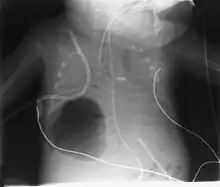

Diagnosis can be made using chest X-ray; the lesion shows up as a small, round area filled with air.[1] Computed tomography can give a more detailed understanding of the lesion.[1] Differential diagnoses – other conditions that could cause similar symptoms as pneumatocele include lung cancer, tuberculosis,[7] and a lung abscess[1] in the setting of hyper IgE syndrome (aka Job's syndrome), as a complication of COVID-19 pneumonitis,[8] or on its own, often caused by Staphylococcus aureus infection during cystic fibrosis.